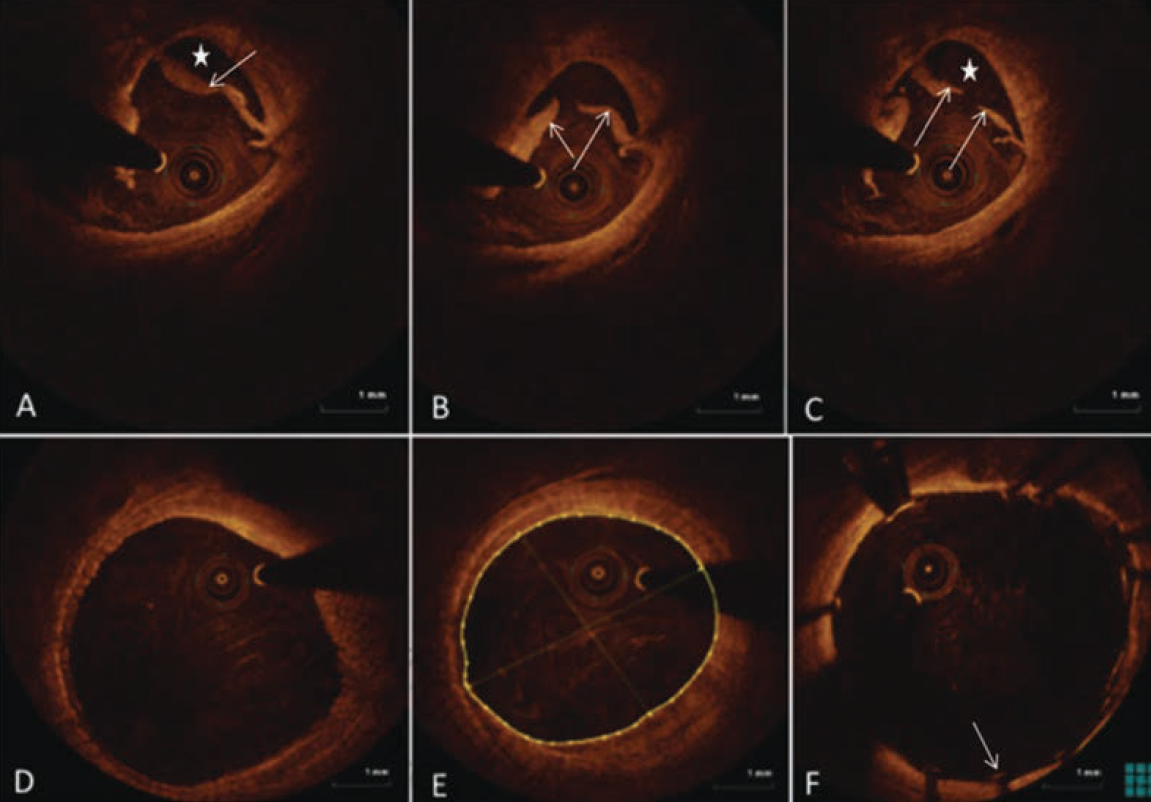

A 62-year-old female with history of hypertension, hyperlipidemia, diabetes, and known PAD was referred for management of lifestyle-limiting claudication of her right lower extremity despite maximal medical therapy. Her right lower-extremity ABI was 0.7, and she was referred for invasive peripheral angiography and possible intervention. A peripheral angiogram showed focal sequential lesions in her right SFA (Figure 3A). Using right groin access, a 6 Fr crossover sheath was placed. An .014-inch guidewire was advanced into the popliteal artery and OCT imaging was performed at baseline (Figure 4A-C). Measurements were made to delineate an accurate reference vessel diameter (Figure 4B-C) as well as minimal luminal diameter (Figure 4A) at the lesion sites. A fibrocalcific plaque was well described at the lesion site (Figure 4A). We performed OCT-guided directional atherectomy of the focal lesions using a Pantheris device (Avinger) (Figure 5A-B), followed by balloon angioplasty with a 6.0 mm x 80 mm drug-coated balloon with good results (Figure 3B-E). Repeat OCT imaging showed plaque removal without any dissection, clot, or residual significant stenosis (Figures 4D and 4F). The patient was treated with dual antiplatelet therapy for 1 month with significant improvement in her symptoms during follow-up.

mammary (IM) catheter for the selective right femoral angiogram after left-to-right crossover. A chronic, subtotally occluded right distal popliteal stenosis extending to the tibioperoneal trunk was identified and we elected to go ahead with a endovascular recanalization approach. The 5 Fr sheath was exchanged for a 6 Fr, 45 cm long sheath. A 300 cm, .014-inch Regalia guidewire (Asahi Intecc) was advanced to the right posterior tibial artery and a baseline OCT was performed (Figure 6). Due to significant calcification identified with OCT, we decided to perform an

orbital atherectomy recanalization using the Diamondback 360 atherectomy device (Cardiovascular Systems, Inc.) in the affected segment. Although atherectomy established excellent angiographic flow, due to mild angiographic “haziness” at the site of intervention, we elected to perform a follow-up OCT (Figure 7). OCT demonstrated multiple segments of endothelial protrusion in the arterial lumen. Although data regarding the clinical significance of such OCT findings is currently absent, we decided to proceed with a 3.5 mm × 100 mm × 150 mm Sterling balloon (Boston Scientific) angioplasty. Final angiographic and OCT imaging showed good results (Figure 8).